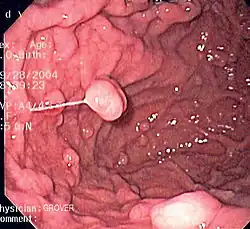

An endoscopy of a normal stomach of a healthy 65-year-old woman

Endoscopic image of a fundic gland polyp